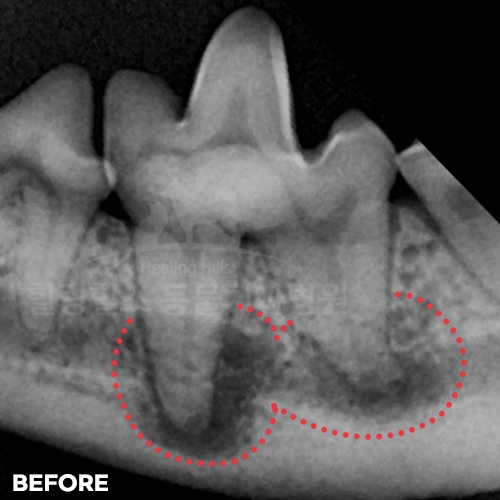

[강아지어금니파절, 치아흡수, 치수괴사, 치근단농양, 치근단공개방....! 편측절제(Hemisection)]

샘플